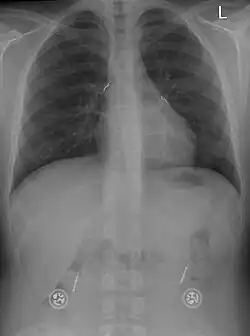

Tetraplegiker mit hoher Querschnittverletzung (oberhalb C3 – siehe segmentale Innervation, Segmente der Wirbelsäule) müssen beatmet werden, da die Anregung (Innervierung) des Zwerchfells über die beiden Phrenikusnerven nicht mehr funktioniert. Früher geschah diese Beatmung mit Hilfe der so genannten eisernen Lunge – heute mit Beatmungsgeräten über ein Tracheostoma. Die funktionelle Elektrostimulation bietet eine Alternative, indem das noch intakte Zwerchfell inklusive der dazugehörigen Motornerven (Nervus phrenicus) für die Atmung wieder aktiviert wird. Ein implantierter Elektrostimulator reizt den/die Phrenikusnerven mit kleinen Elektroden, die dort angenäht sind. Das Zwerchfell kontrahiert sich und erzeugt dadurch einen Unterdruck in der Lunge.